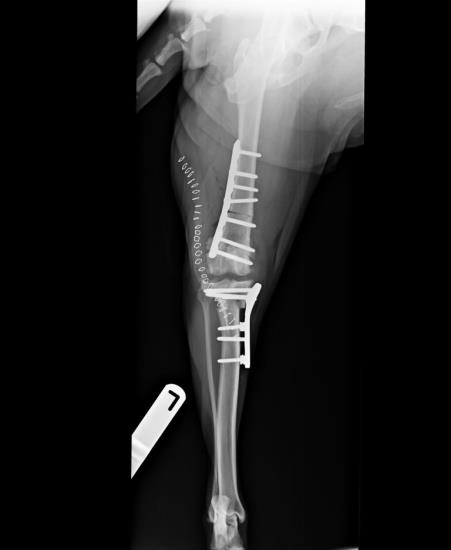

Cranial closing wedge ostectomy (CCWO)

CCWO achieves tibial plateau levelling in a different way to TPLO but will have similar biomechanical effects. We use CCWO for dogs with proximal tibial deformity leading to angulation between the proximal and distal tibial axes. This includes many small breed dogs with cranial cruciate ligament disease. It is an effective way to treat cranial cruciate ligament disease in juvenile dogs where implants cannot be placed across the open physes, allowing unimpeded continued growth of the tibia (Figure 2).

Figure 2. Treatment of cranial cruciate ligament rupture in a West Highland white terrier using a cranial closing wedge ostectomy stabilised with a locking plate and screws